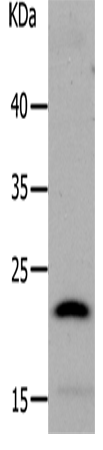

分类: 科研抗体货号: P11292别名: DTD, QR1, DHQU, DIA4, NMOR1, NMORI应用: WB,IHC反应种属: Human, Mouse, Rat